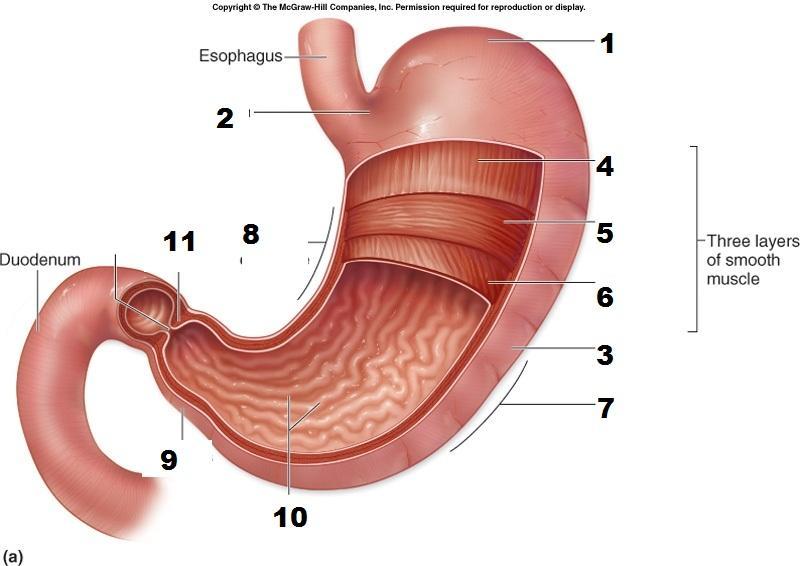

Body (of stomach)

Cardia (of stomach)

Fundus (of stomach)

Gastroesophageal sphincter

Pyloric Sphincter

Pylorus (of stomach)

Rugae (of stomach)

Inner circular layer (of muscular externa)

Outer longitudinal layer (of muscular externa)